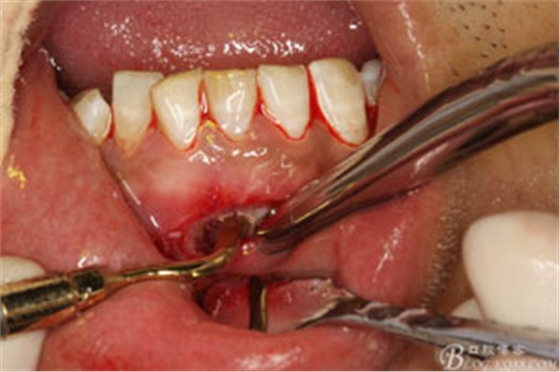

圖8.超聲骨刀去除根尖周圍感染骨質(zhì)

圖9.清晰可見牙膠從31根尖1/3溢出。